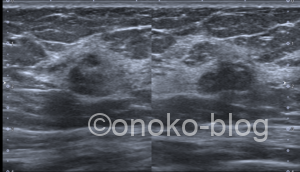

低エコー…域?腫瘤?

ここだけ乳腺が厚めだし、テクスチャーが周りと違うんですよね…

しっかり腫瘤形成してます!な感じではないような…

でも、うーん…分葉状にも見えるような…

カラードプラでは辺縁に血流を認めます。

(だいぶゲイン上げてます)